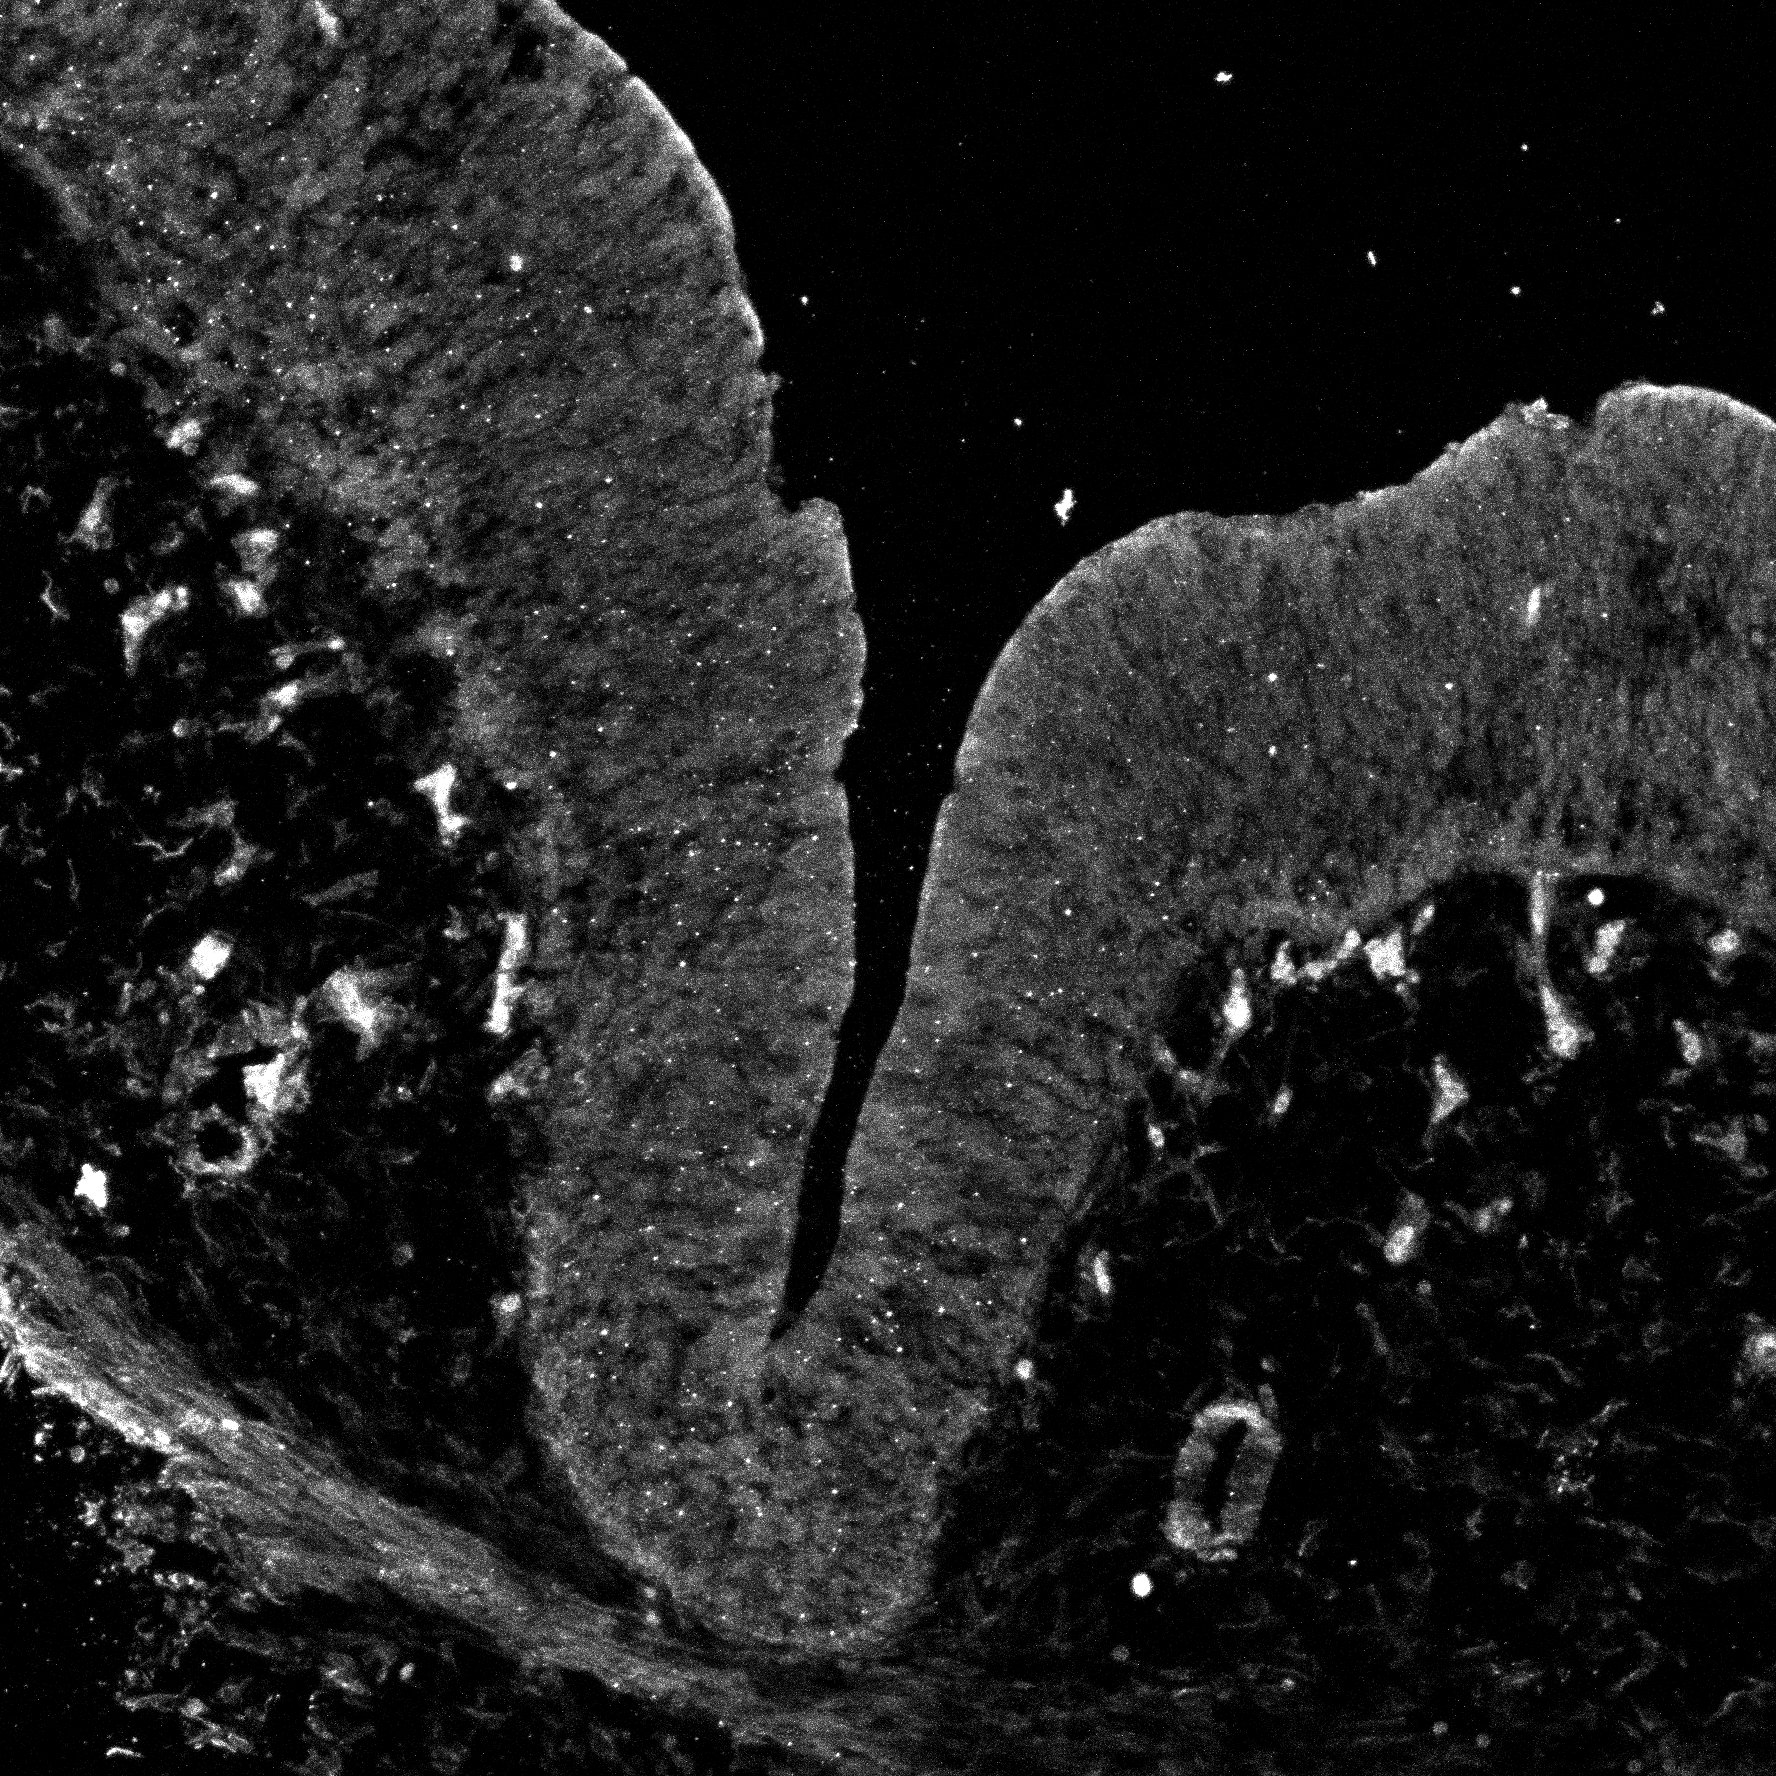

An anatomical analysis of the developing human midbrain from 6 post-conceptional weeks (PCW) to 22 PCW reveals increased tissue complexity, characterized by the emergence of dopaminergic nuclei, as highlighted by immunofluorescence analysis for tyrosine hydroxylase (TH).

MAP2

11PCW human midbrain